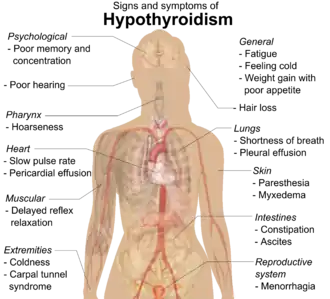

Systemic manifestations of hypothyroidism

As lymphocytic infiltration progresses, patients may exhibit signs of hypothyroidism in multiple bodily systems, including, but not limited to, a larger goiter, weight gain, cold intolerance, fatigue, myxedema, constipation, menstrual disturbances, pale or dry skin, and dry, brittle hair, depression, and ataxia.[14][10] Extended thyroid hormone deficiency may lead to muscle fibre changes, resulting in muscle weakness, muscle pain, stiffness, and rarely, pseudohypertrophy.[15] Patients with goiters who have had autoimmune thyroiditis for many years might see their goiter shrink in the later stages of the disease due to destruction of the thyroid.[1] Graves disease may occur before or after the development of autoimmune thyroiditis.[16]

While rare, more serious complications of the hypothyroidism resulting from autoimmune thyroiditis are pericardial effusion, pleural effusion, both of which require further medical attention, and myxedema coma, which is an endocrine emergency.[10]

Many symptoms are attributed to the development of Hashimoto's thyroiditis. Symptoms can include: fatigue, weight gain, pale or puffy face, feeling cold, joint and muscle pain, constipation, dry and thinning hair, heavy menstrual flow or irregular periods, depression, a slowed heart rate, problems getting pregnant, miscarriages,[17] and myopathy.[15] Some patients in the early stage of the disease may experience symptoms of hyperthyroidism due to the release of thyroid hormones from intermittent thyroid destruction[10][18] (also called "destructive thyrotoxicosis").[5] In non-medical settings, the term "flare" is used to refer to a sudden exacerbation of symptoms, whether hyper or hypo.[19]

While most symptoms are attributed to hypothyroidism, similar symptoms are observed in Hashimoto's patients with normal thyroid hormone levels.[20][21][13] According to one study, these symptoms may include lower quality of life, and issues of the "digestive system (abdominal distension, constipation and diarrhea), endocrine system (chilliness, gain weight and facial edema), neuropsychiatric system (forgetfulness, anxiety, depressed, fatigue, insomnia, irritability, and indifferent [sic]) and mucocutaneous system (dry skin, pruritus, and hair loss)."[22]